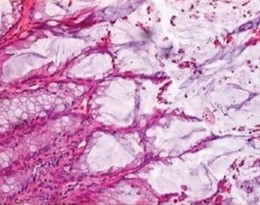

Μικροσκοπική εικόνα μετά από χρώση αιματοξυλίνης-ηωσίνης, που αναδεικνύει ινώδη συνδετικό ιστό χωρίς ατυπία, ομοιάζοντας με δερματικό ίνωμα (Ευγενική παραχώρηση Dr. V. Penopoulos)